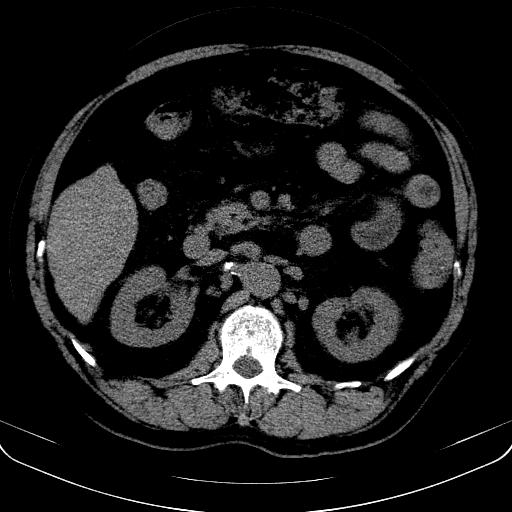

以下是引用jia119在2008-3-5 13:31:00的发言:[br]肝内多发片状低密度影,密度不均,我还是考虑肝ca可能,另肝内小囊肿,胆囊增大。

以下是引用形影不离在2008-3-5 12:18:00的发言:[br]肝硬化伴门脉高压征,肝内占位待排,增强再说.

以下是引用随光逐影在2008-3-5 21:11:00的发言:[br]肝硬化伴门脉高压(食管下段静脉曲张),肝癌不排除。建议:行ct增强扫描检查。

以下是引用同在2008-3-5 13:56:00的发言:[br]考虑肝癌可能性大,胆囊增大.